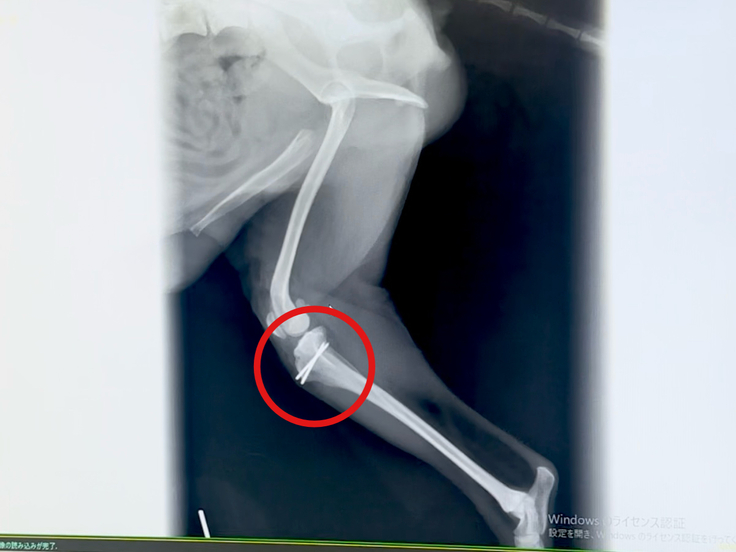

手術後はしっかりとお皿の位置が正常に戻り、曲がっていた骨も真っ直ぐと矯正されていました。

骨が歪んでいたので切断し2本のピンで固定しています。